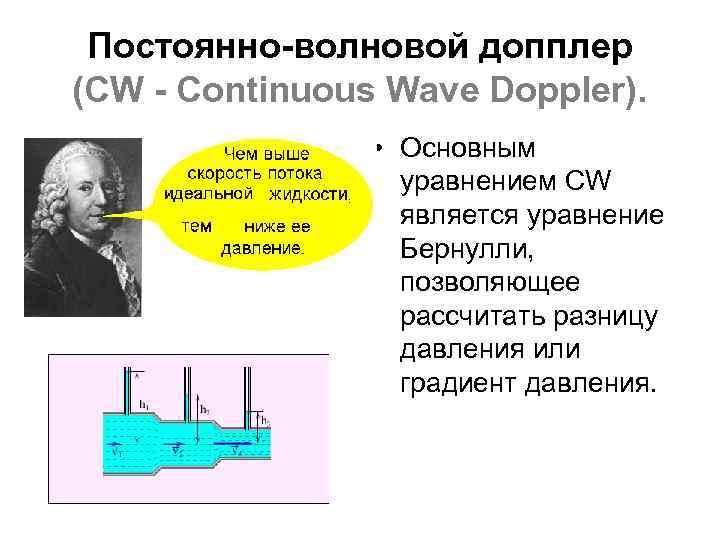

Постоянно-волновой допплер (CW - Continuous Wave Doppler). • Основным уравнением CW является уравнение Бернулли, позволяющее рассчитать разницу давления или градиент давления.

Постоянно-волновой допплер (CW - Continuous Wave Doppler). • Основным уравнением CW является уравнение Бернулли, позволяющее рассчитать разницу давления или градиент давления.